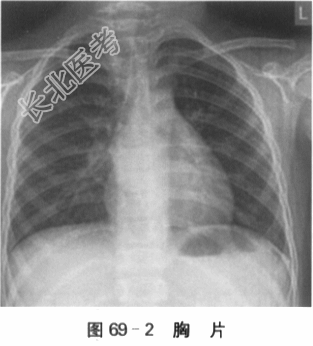

(2)X线胸片检查:胸廓对称,两肺纹增多,两肺未见明显渗出影。两侧肺门影不大,心影稍饱满,CTR约为56%,纵隔无明显增大。两隔面光整,肋膈角锐利。如图69-2所示。